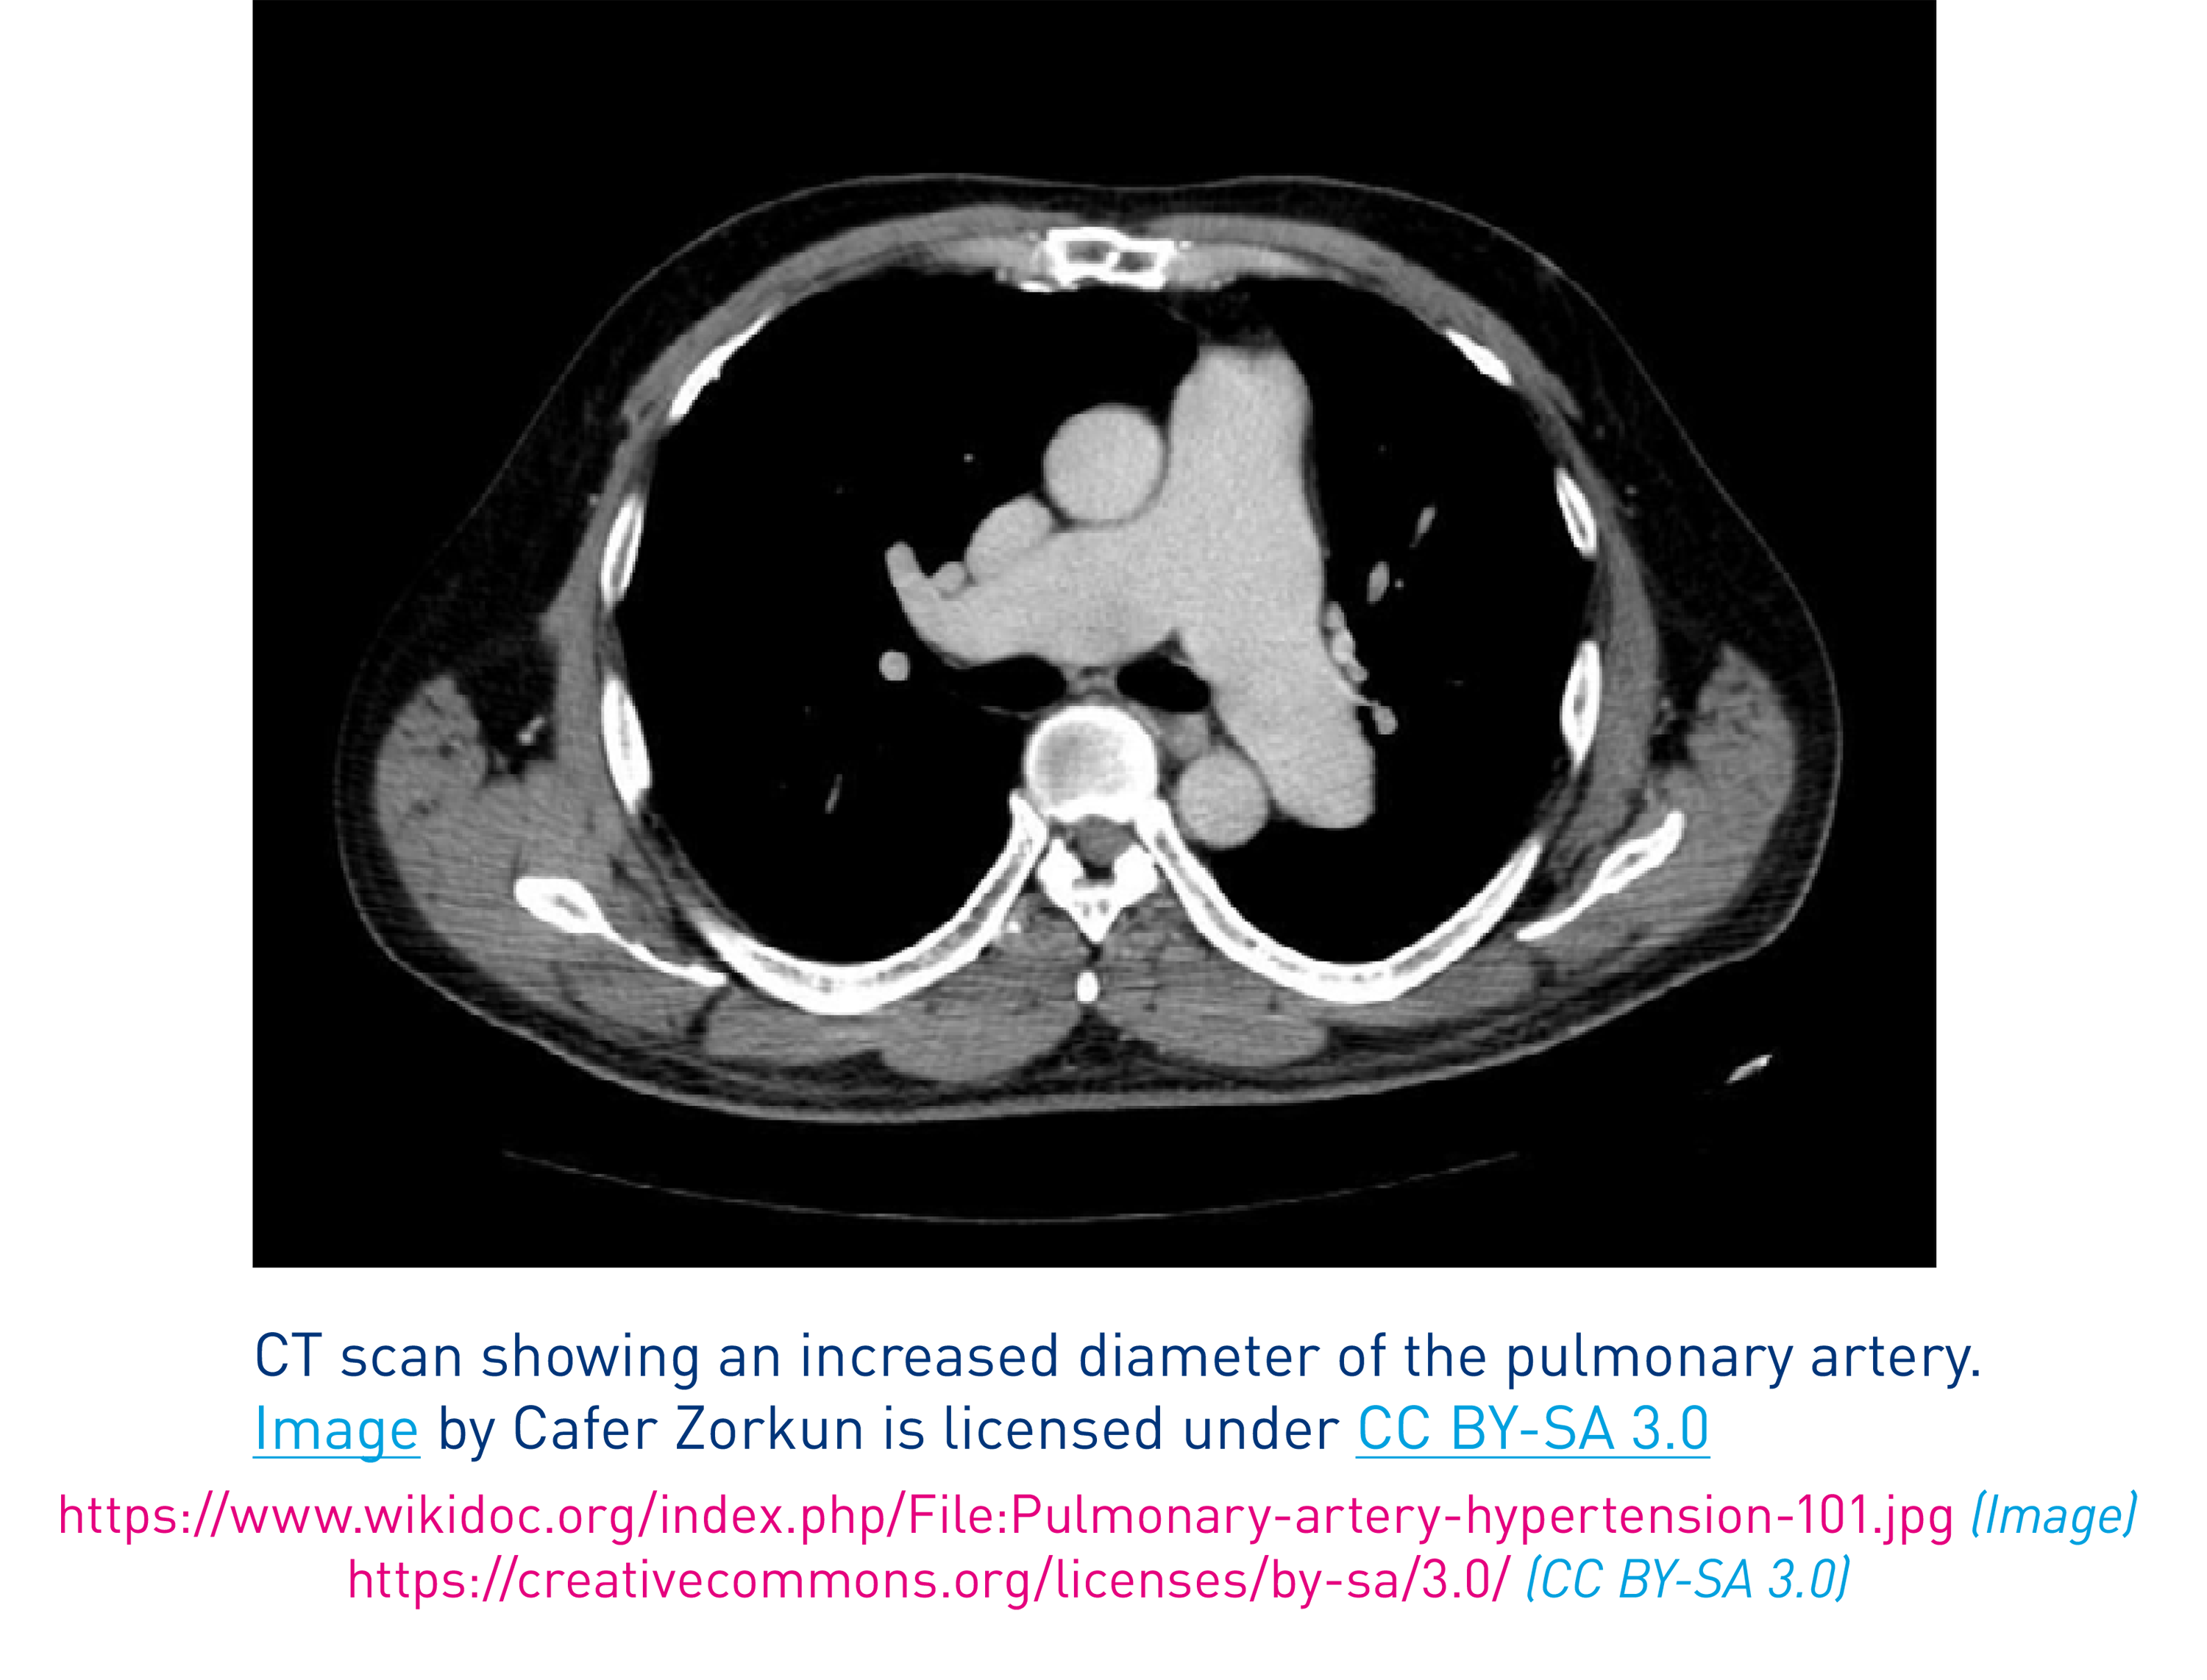

When PAH is suspected, clinical history, symptoms, signs, electrocardiogram (ECG), chest radiograph, echocardiogram, PFTs, CT of the chest and a V/Q scan are all required in order to exclude diagnosis of left heart disease, lung disease or chronic thromboembolic pulmonary hypertension (CTEPH). To confirm diagnosis of PAH, referral to a PH specialist centre for Right Heart Catheterization is required.3

There are several other key investigations you can perform to raise suspicion of PH and help identify and classify its cause. Note that right heart catheterisation (RHC) is required to confirm a diagnosis of PAH, and should be performed by a PH centre.3